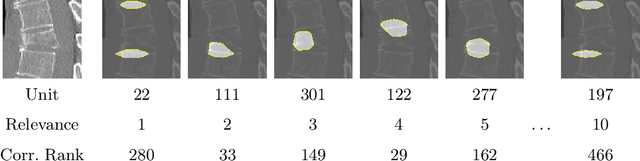

Abstract:Do black-box neural network models learn clinically relevant features for fracture diagnosis? The answer not only establishes reliability quenches scientific curiosity but also leads to explainable and verbose findings that can assist the radiologists in the final and increase trust. This work identifies the concepts networks use for vertebral fracture diagnosis in CT images. This is achieved by associating concepts to neurons highly correlated with a specific diagnosis in the dataset. The concepts are either associated with neurons by radiologists pre-hoc or are visualized during a specific prediction and left for the user's interpretation. We evaluate which concepts lead to correct diagnosis and which concepts lead to false positives. The proposed frameworks and analysis pave the way for reliable and explainable vertebral fracture diagnosis.